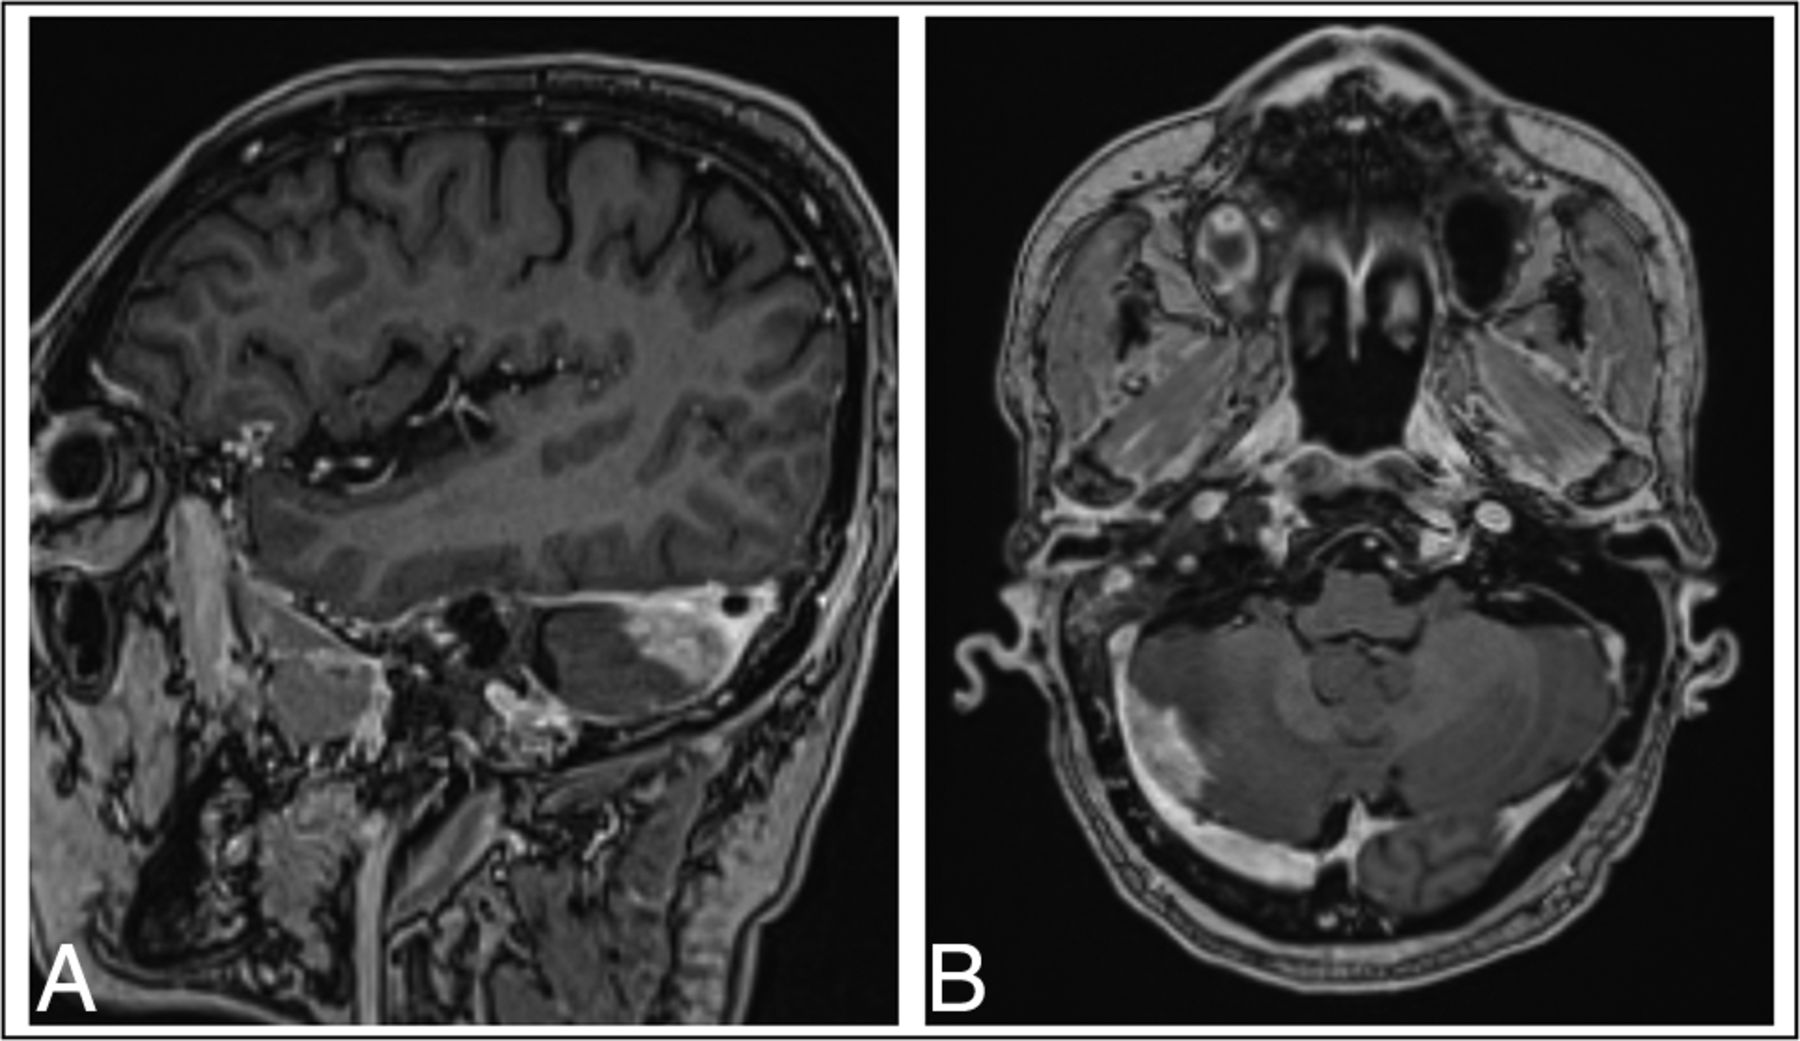

Brain MR imaging for patient 1, a 67-year-old woman with locally advanced EGFRm NSCLC. Sagital (A) and axial (B) projections show enhancement along the parenchyma, with ring-enhancing lesions extending into the right parietal sulci in continuity. The scan was performed for restaging purposes, before any brain-directed treatment.